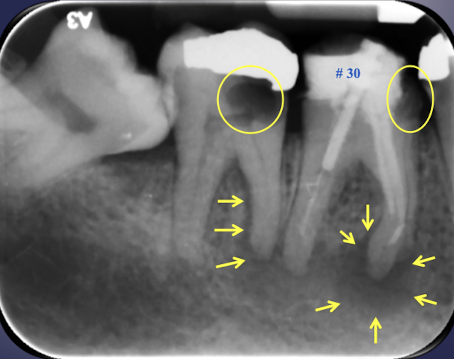

what are some potential results of periapical inflammation that all present identically radiographically?

parulis aka gum boil

periapical granuloma

periapical cyst

periapical abscess

condensing osteitis

which potential result of periapical inflammation?

inflamed granulation tissue at intraoral opening of sinus tract

classically dome-shaped yellow-pink papule; rarely hyperplastic soft tissue mass that may mimic pyogenic granuloma or other pathology ie exophytic hyperplastic perulis on adj tooth assocxiated w non-vital tooth

usually on gingiva facial to non-vital tooth

may or may not exhibit active suppuration

parulis

parulis; not easy to pulp test teeth that are equidistant to this sinus tract extrusion

localized area of bone sclerosing

aka focal sclerosing osteitis (radiopaque)

treatment:Â

endodontic therapy or extraction of offending tooth

85% of cases will resolve or regress

bone scar may result following resolution of inflammation